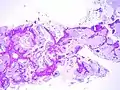

The criteria for diagnosing pulmonary adenocarcinoma have changed considerably over time.[10][11] The 2011 IASLC/ATS recommendations, adopted in the 2015 WHO guidelines, use the following criteria for adenocarcinoma in situ: [12]

- tumor ≤3 cm

- solitary tumor

- pure "lepidic" growth*[13]

- No stromal, vascular, or pleural invasion

- No histologic patterns of invasive adenocarcinoma

- No spread through air spaces

- Cell type mostly nonmucinous

- Minimal/absent nuclear atypia

- ± septal widening with sclerosis/elastosis

* lepidic = (i.e. scaly covering) growth pattern along pre-existing airway structures

A true diagnosis of AIS can only be made once the entire tumor has been surgically removed, because it must be evaluated for evidence of microscopic invasion into the adjacent normal lung. Findings of malignant invasion would mean that the tumor must be reclassified as invasive adenocarcinoma.